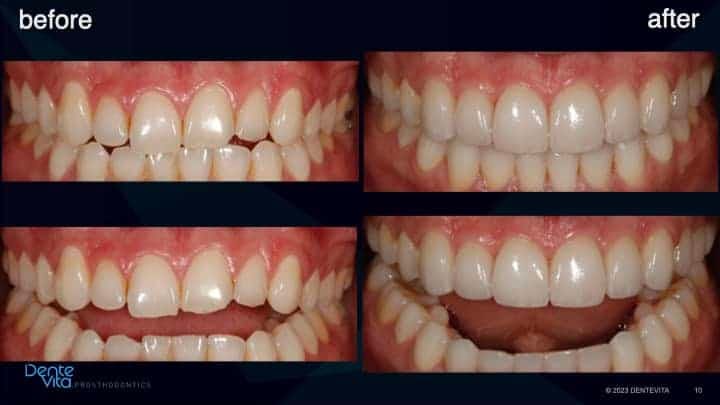

Tooth enamel wear and erosion, with resultant short/smaller teeth dimensions and associated vertical and horizontal tooth drift.

This case study addressed significant tooth erosion from gastric reflux. Lost vertical space from vertical tooth drift was reversed with orthodontic treatment (intrusion and alignment therapy).

After completion of successful orthodontic therapy, missing tooth structure was rehabilitated/restored with conservative 360 degree and three-quarter porcelain veneer therapy, along with posterior occlusal partial coverage onlay restorations.

Photos of the patients original smile taken prior to the damage caused from erosion/wear were utilized to help design correct tooth form, dimensions and color characteristics of the definitive aesthetic and functional restorations.